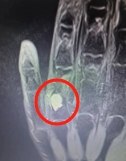

术前X光片

术中